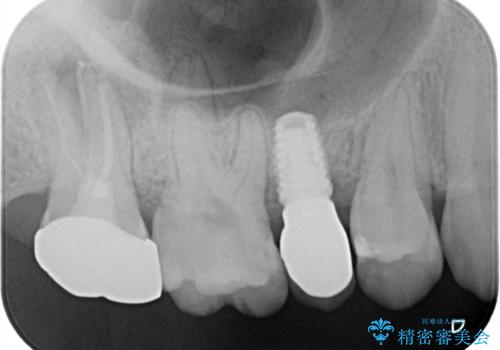

治療回数を短くしたいと1DAYインプラントを希望されました。

インプラント埋入手術は1回で全て行い、2ヶ月後にはセラミック治療で、審美回復と機能回復をしました。

来院回数が少なく、しっかり食事もできるとの事で非常に喜んで頂けました。